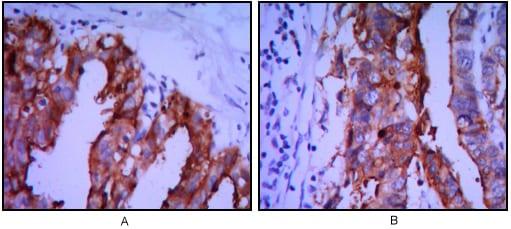

使用ALPP小鼠单抗(DAB染色)对石蜡包埋的人卵巢癌(A)和胃癌(B)组织进行免疫组化分析。